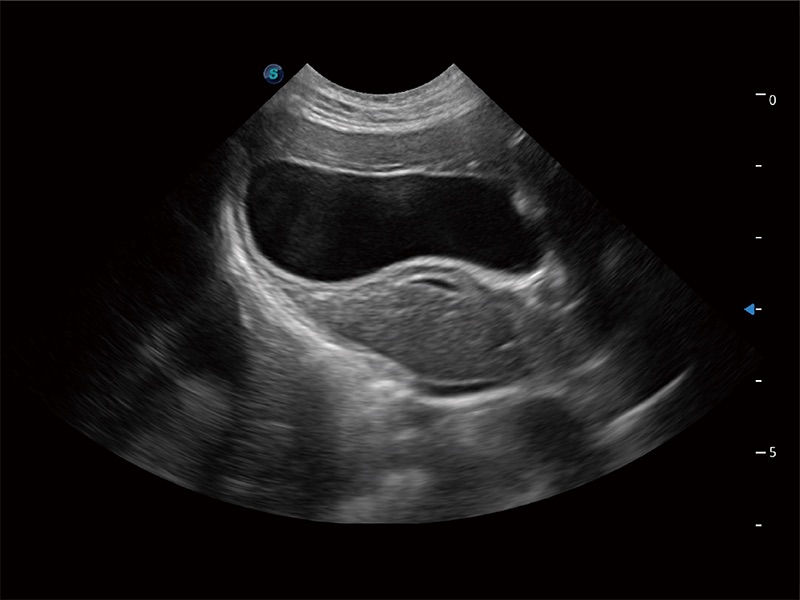

高性能和先進(jìn)的臨床應(yīng)用工具可以為動(dòng)物醫(yī)生提供臨床信心。ProPet 80 搭載了先進(jìn)的腹部和淺表應(yīng)用工具,幫助醫(yī)生在日常臨床實(shí)踐中發(fā)揮前所未有的作用。

極大提升超低速微細(xì)血流的檢出能力,同時(shí)更精準(zhǔn)地濾除軟組織和超聲信號(hào),為獸用醫(yī)生提供以往無(wú)法通過(guò)常規(guī)血流獲得的疾病診斷信息。